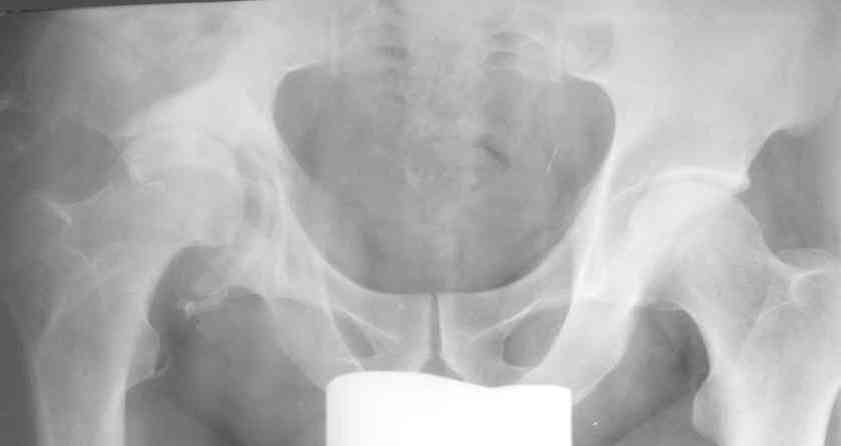

Застарелый вывих бедра

К нам обратился житель Казахстана с застарелым вывихом бедра.

Травма год назад, вместо синтеза заднего края казахскими умельцами установлена клинковая пластина, через 6 мес удалена. Больной ходит с тростью,сгибание в т-б 90, разгибание 170, укорочение 5 см, боли не выражены, анальгетиками не пользуется. Настроен на эндопротезирование в клинике, где есть опыт подобных операций (возможно за рубежом). Наш план: аппарат таз-бедро, постепенное низведение бедра, "октопус" с пластикой. Но с такими большими дефектами мы не сталкивались. Есть вариант сначала аппарат, затем реконструкция впадины, протез обычный через 4-6 мес. Есть мнение не восстанавливать длину. Будем признательны за полезные советы. Было бы интересно посмотреть пример.